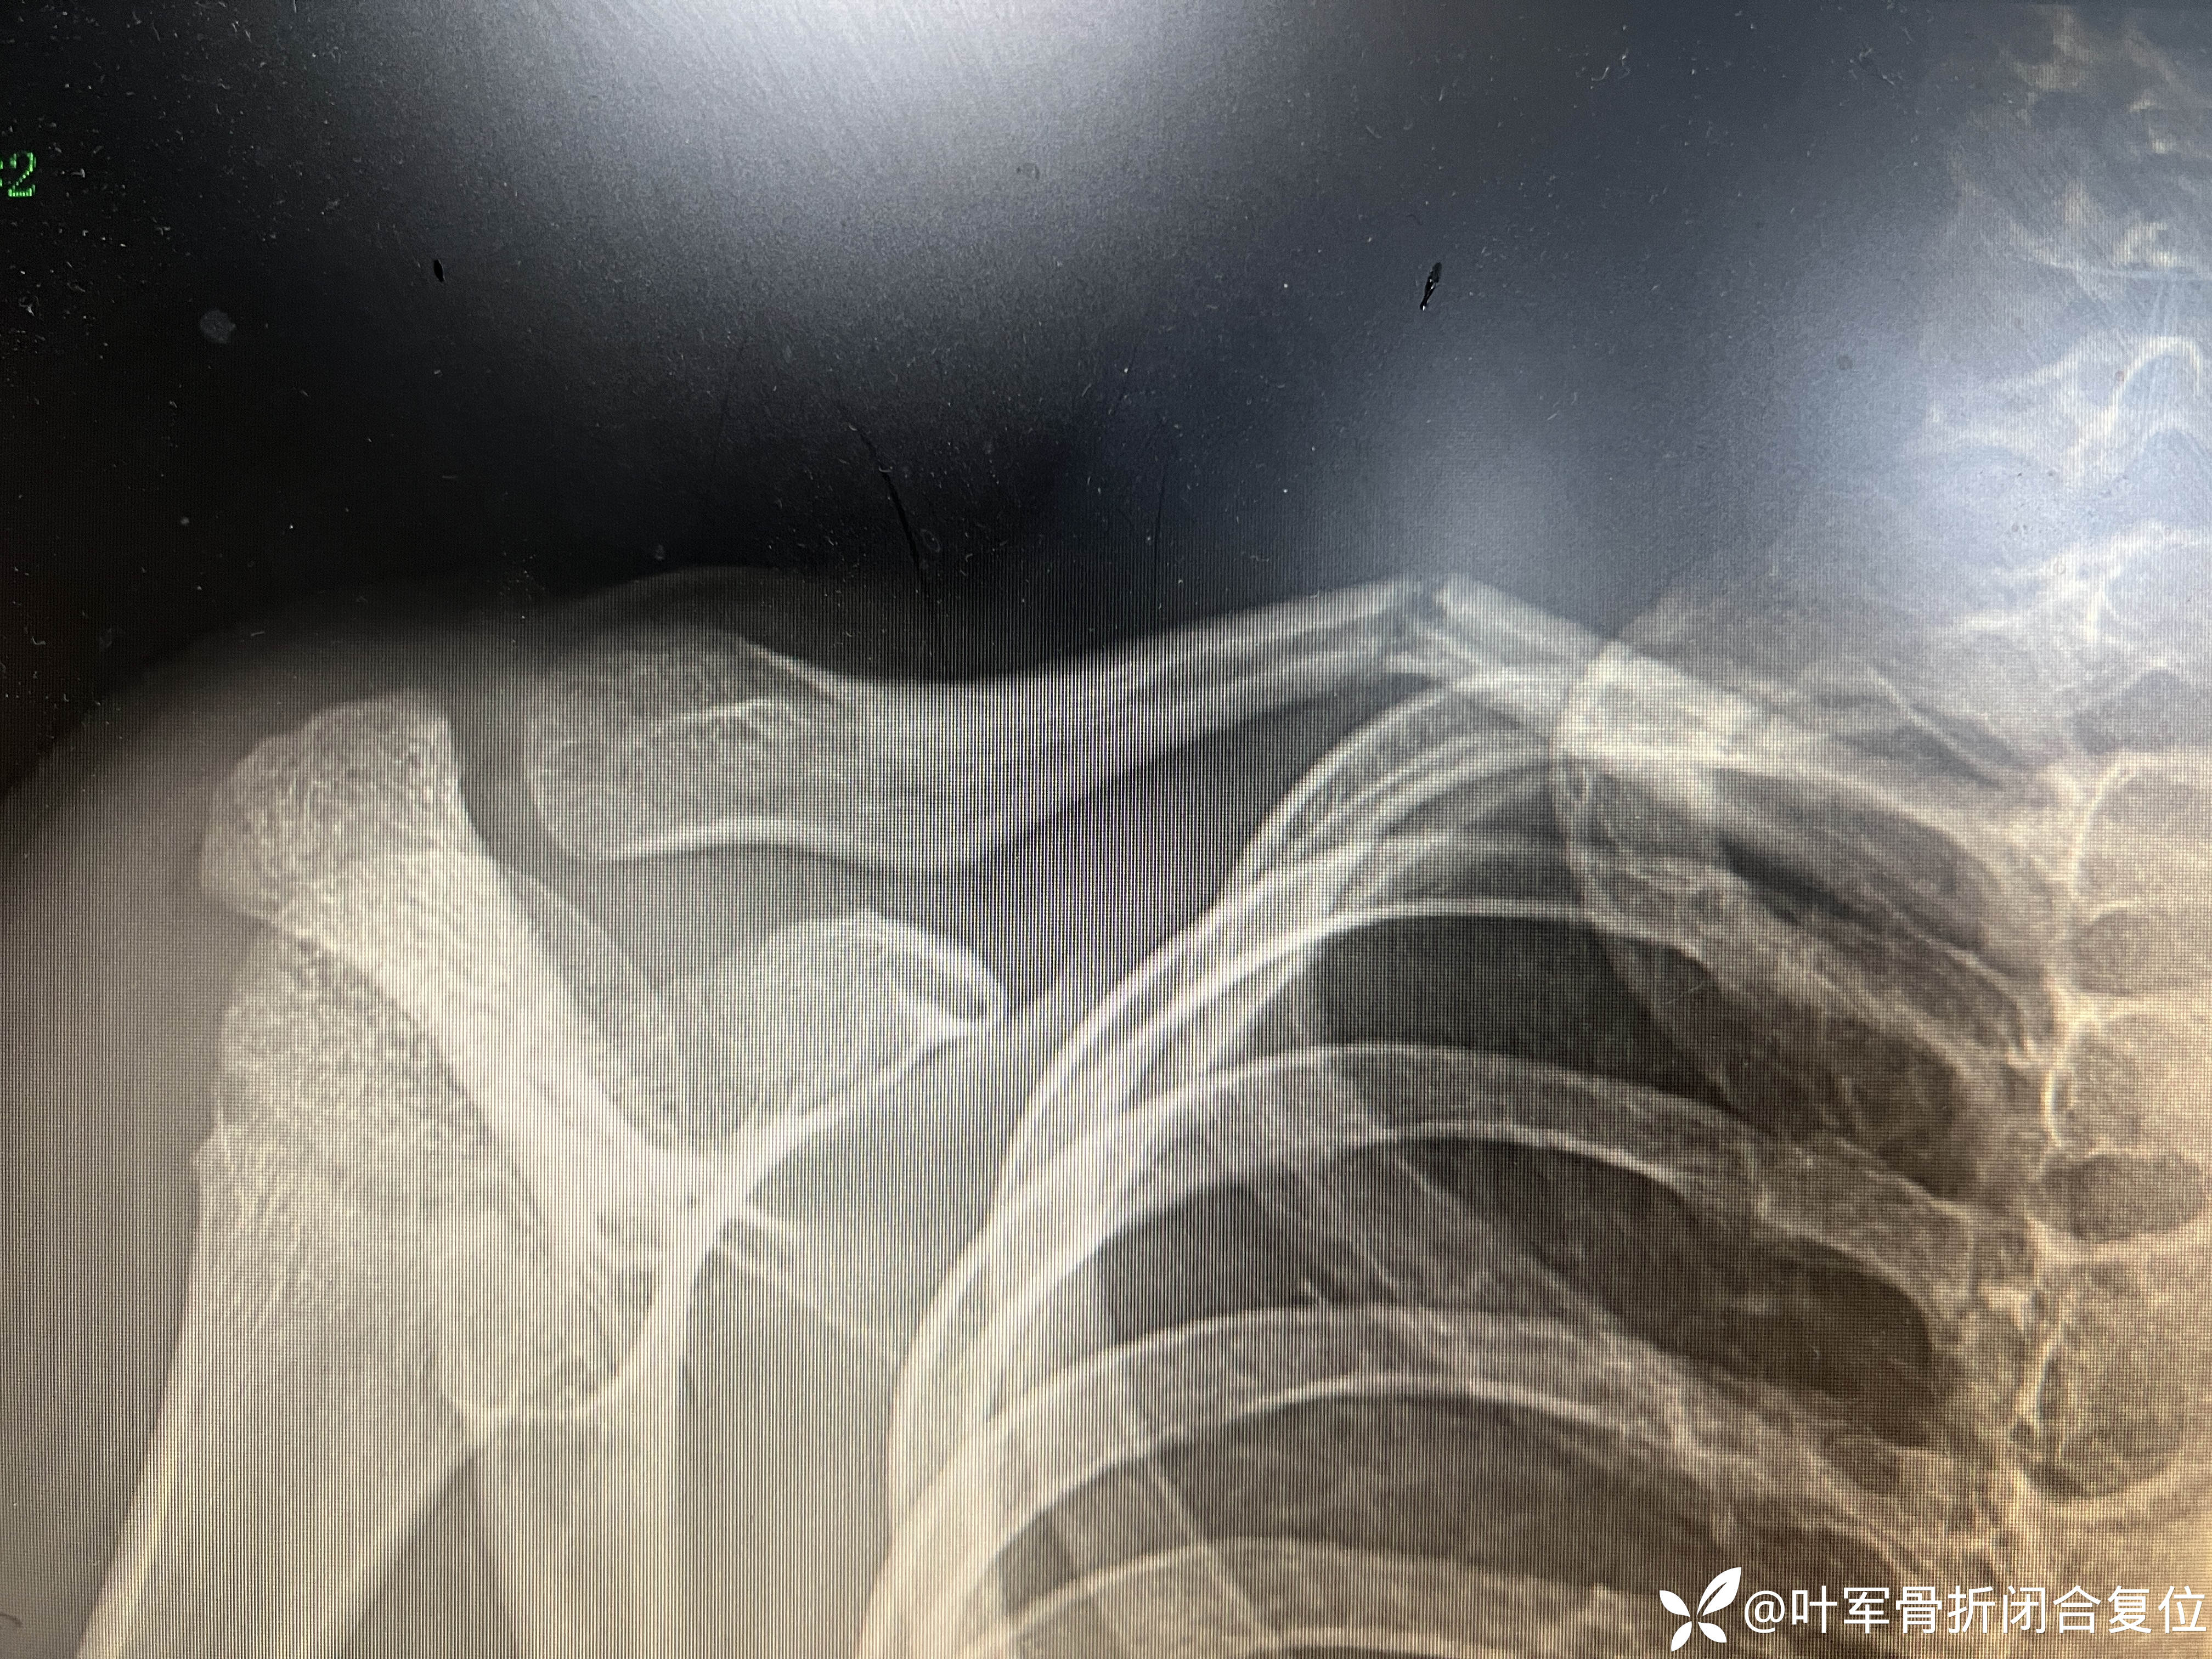

11岁儿童锁骨骨折 成角畸形

对侧锁骨